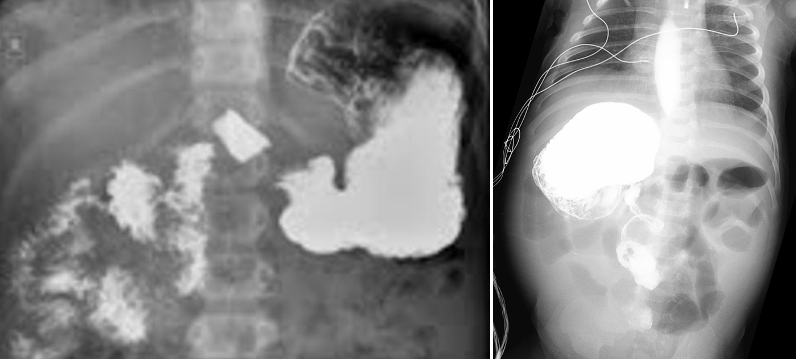

진단: 단순 복부 X선 사진에서 특징적인 Double bubble sign 확인

복부 X선: 위장과 십이지장에는 가스가 있고, 나머지 창자에는 가스가 없음

표준 진단: 상부위장관 조영술(UGI series)로 십이지장과 공장의 위치 확인

→ 십이지장, 공장 연결부가 중심선의 우측에 존재, 소장은 복강 우측에, 대장은 좌측에 존재

→ corkscrew appearance: 특징적 소견